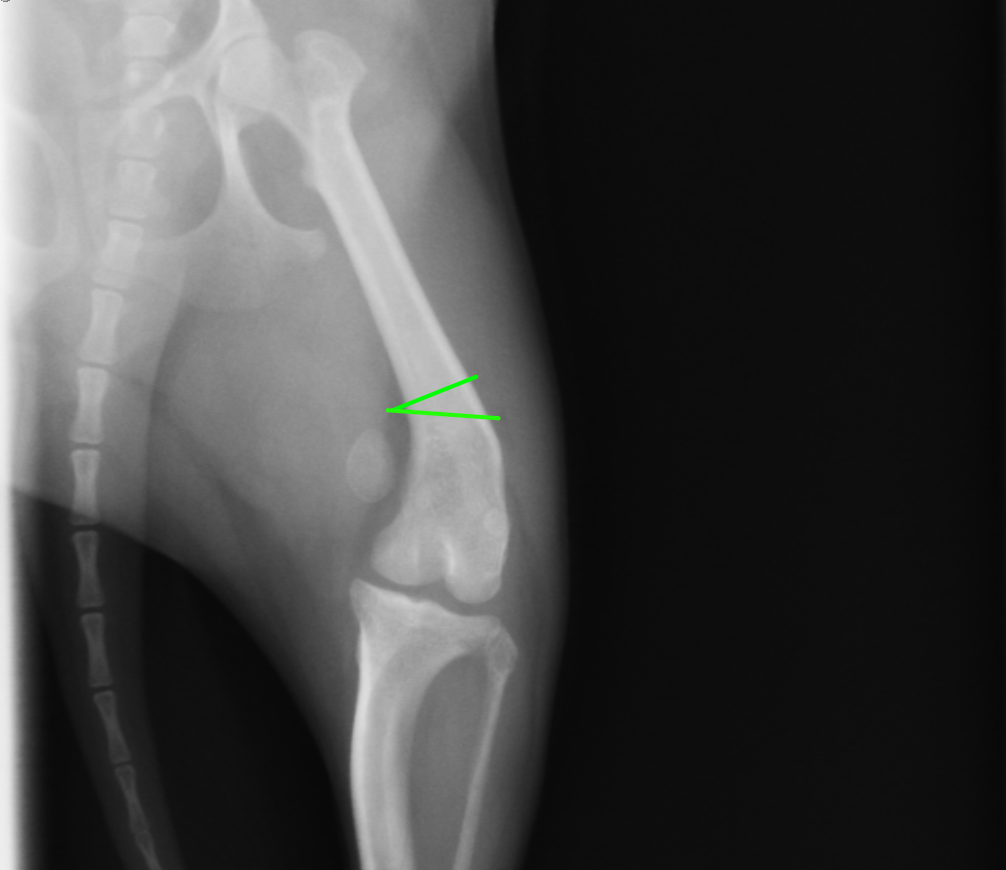

にプラスして大腿骨の矯正骨切術を追加する場合があります。パテラの脱臼に大腿骨の湾曲変形が大きく関わっているからです。この術式の場合には骨の一部を楔形に切断し、プレートで再度固定するという術式を実施します。

緑の線で骨を一度切断します。実際には3次元的に湾曲変形しているため、側面からの捻れ湾曲も考慮が必要です。